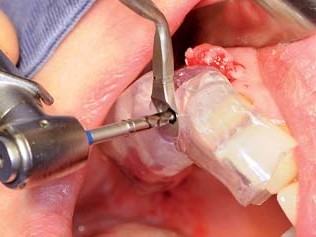

Der Knochenring wurde entsprechend dem Bohrprotokoll für das 4,1-mm-Implantat extrakorporal mit dem passenden Einmalbohrer aufbereitet. Danach wurde das Straumann Bone Level Roxolid-Implantat (Ø 4,1 mm, Länge 8 mm) extrakorporal maschinell in den homologen Knochenring, der mit der bonering fix-Zange gehalten wurde, eingebracht (Abb. 17). Anschließend wurde das Implantat samt Knochenring in die Implantatbettregion der Mundhöhle verbracht und entsprechend subkrestal maschinell versenkt (Abb. 18). Nach Entfernung der Loxim-Einbringhilfe wurden beide Implantate mit Verschlussschrauben versehen. Der Resorptionsschutz erfolgte mittels synthetischem biphasischen Kalziumphosphat¹⁷ eine Abdeckung des Augmentats (Abb. 19). Zusätzlich fand eine Membran aus porcinem Perikard ihre Anwendung.¹⁸ Abschließend erfolgte der typische spannungsfreie Naht-Wund-Verschluss. In der Frontzahnregion wurde eine präoperativ gefräste PMMA-Kunststoffbrücke eingesetzt (Abb. 20), die im Bereich des Zwischengliedes eine belastungsfreie Einheilung des Straumann PURE Ceramic Implantat gewährleistet. Im Seitenzahnbereich verblieb die Zahnlücke auf Wunsch der Patientin unversorgt, da ein gaumenüberspannender Zahnersatz nicht toleriert wird. Das abschließende Orthopantomogramm zeigt die Implantat- und Augmentationssituation radiologisch (Abb. 21).

Abb 16 Extrakorporale Knochenringpräparation

Abb. 16: Extrakorporale Knochenringpräparation